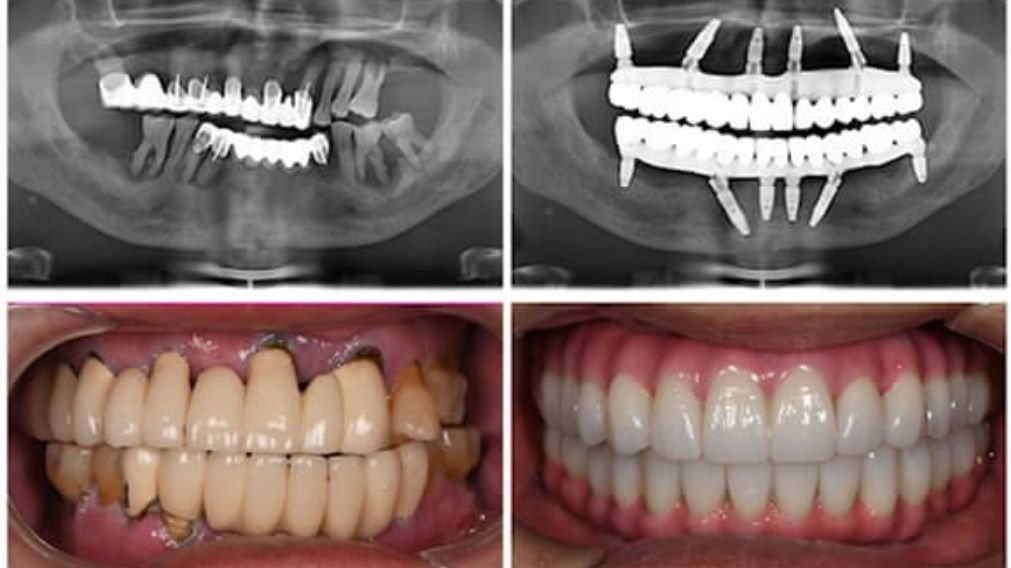

O conceito All-on-6 é uma evolução da técnica All-on-4, projetado para oferecer um nível superior de estabilidade e distribuição de força. Assim como o All-on-4, ele se destina a pacientes que perderam todos os dentes de uma arcada. A diferença fundamental, como o nome sugere, está no número de implantes: em vez de quatro, seis implantes de titânio são cirurgicamente inseridos no osso maxilar ou mandibular para suportar a prótese fixa completa.

Esses dois implantes adicionais não são meros coadjuvantes; eles desempenham um papel biomecânico crucial. Ao aumentar o número de pilares de sustentação, a carga mastigatória é distribuída de forma mais equilibrada por toda a arcada, reduzindo o estresse sobre cada implante individual. Isso não só aumenta a longevidade do tratamento, mas também proporciona uma fundação mais robusta, especialmente em cenários clínicos mais desafiadores.